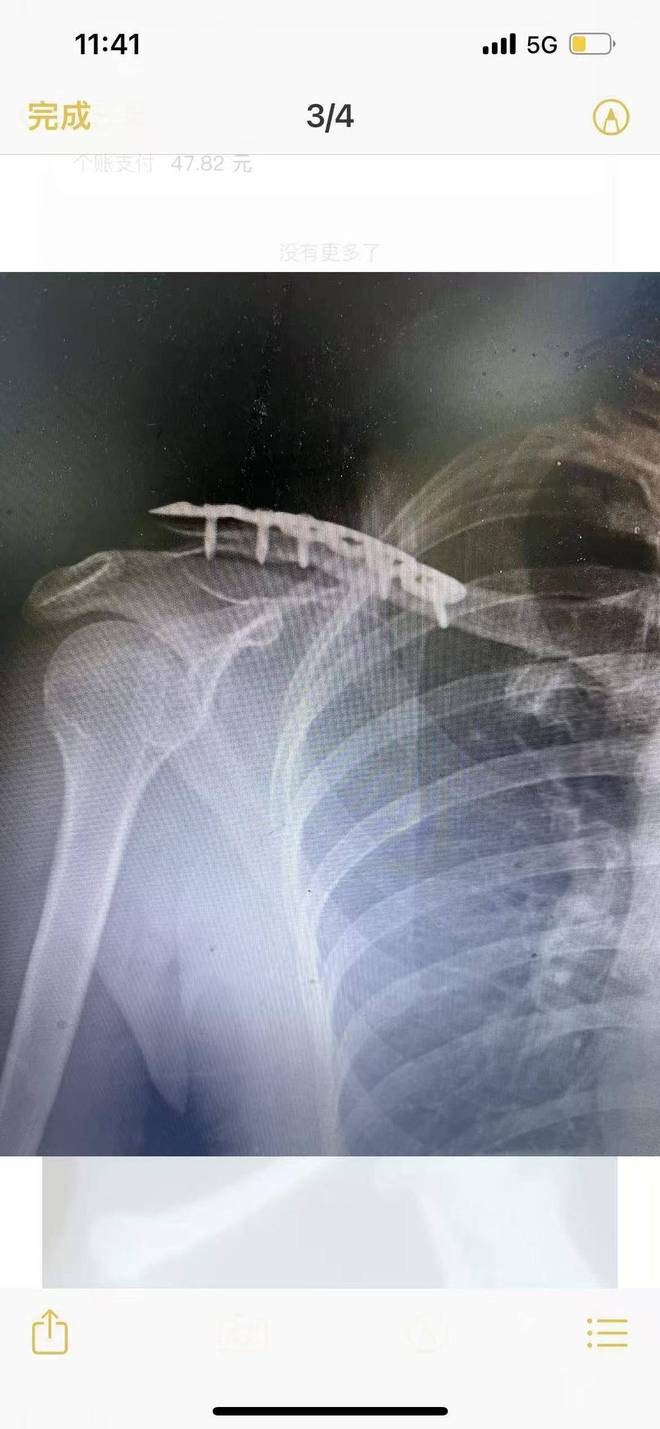

刘女士回忆,由于不确定是否骨折,她先自行前往机构附近的医院拍片,结果诊断显示右侧锁骨断裂。机构一老师得知后,称有熟人可介绍医院进行治疗,刘女士便跟随前往。经检查,她被确诊为右侧锁骨骨折,且医生明确这是新伤。随后,她接受了手术,“手术是半麻,我全程清醒,看着医生把我右边锁骨打开,放进去一块钢板和 7 颗钢钉,那种恐惧感这辈子都忘不了。”

如今,距离受伤已过去四五个月,刘女士的恢复状况并不理想。“我的右手背到后背会痛、吃力,抬也抬不直,还不能提重物。”她无奈地表示,明年还需进行第二次手术取出钢板,预计费用约1—2万元,而手术留下11厘米的疤痕,更是成了她难以磨灭的印记,“前三个月,我每次洗澡看到这个疤都会哭,感觉都要得抑郁症了。”